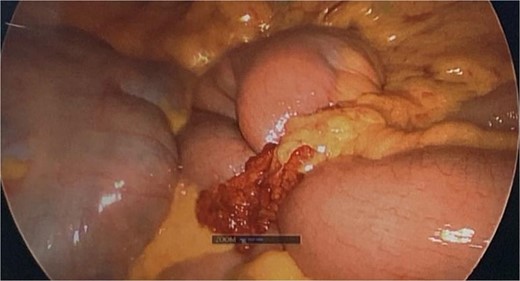

During diagnostic laparoscopy, a loop of jejunum was found to be transomentally herniated, congested but viable (Figs 2 and 3). Adhesiolysis was performed, and no small bowel resection was required. The patient was discharged on postoperative day 2 after an uneventful recovery and has not experienced any complications since.

Intraoperative image from diagnostic laparoscopy showing a loop of jejunum herniating through a defect in the greater omentum.